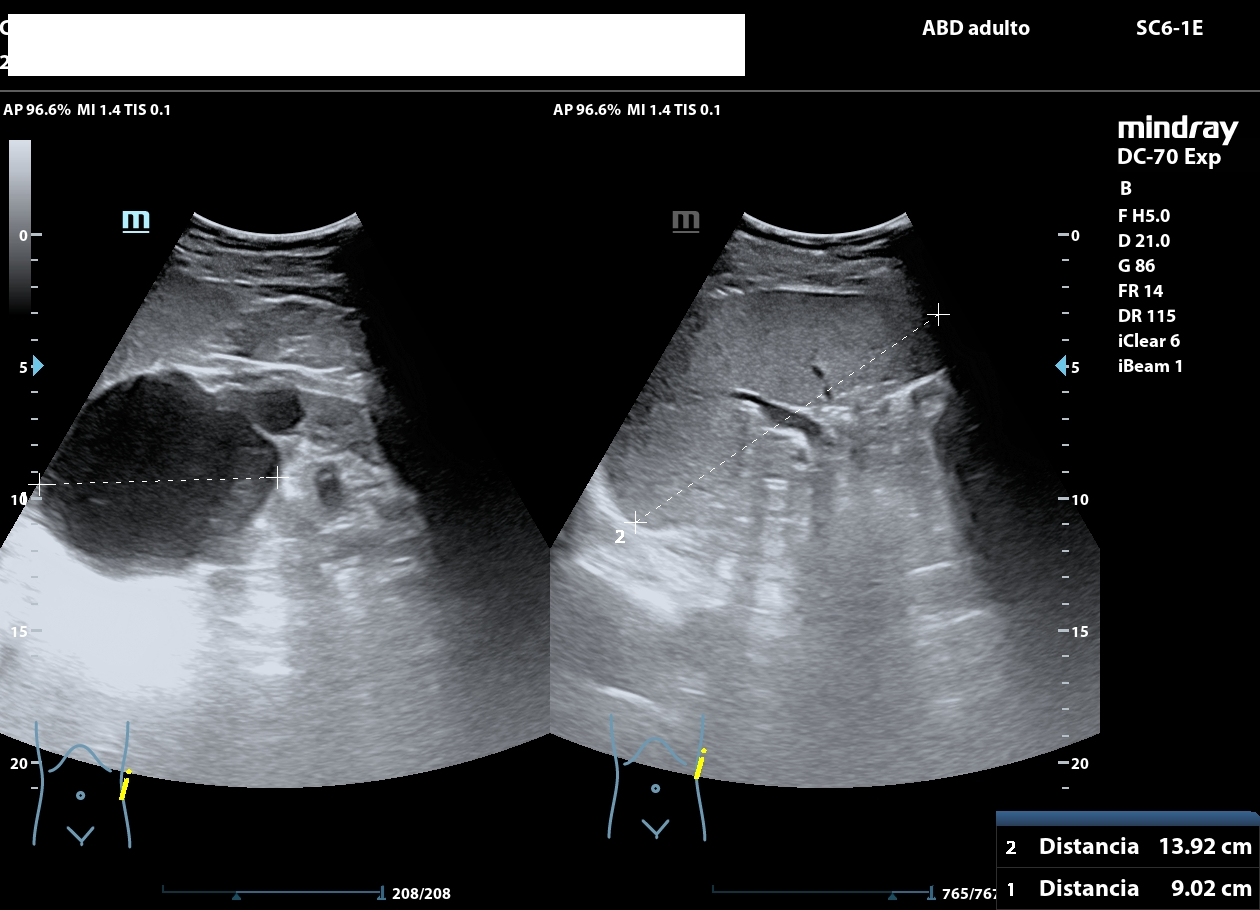

La ecografía abdominal muestra ambos riñones con múltiples quistes corticales y medulares, de diferentes diámetros, distribuidos de forma difusa.

El parénquima presenta un aspecto multiquístico que confiere una morfología global cribo forme, semejante visualmente a un «queso gruyere». No se observan litiasis, ni signos de obstrucción de la vía urinaria.

El quiste de mayor tamaño (aprox. 9 cm) se observa en riñón izquierdo; sin ecos internos, calcificaciones o sextos (categ BosniaK 2). En riñón derecho se aprecian múltiples quistes alguno de ellos con esto grueso en su interior, sin calcificaciones ni componentes sólidos en su interior (categ. BosniaK 2-3).